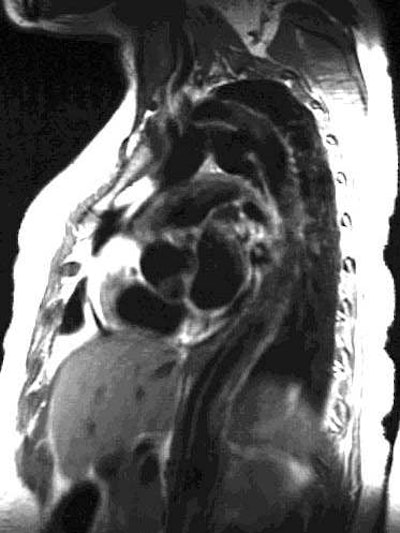

Oblique sagittal SE images showing the flap originate adjacent to the origin of the left subclavian artery and

extending down into the abdomen: